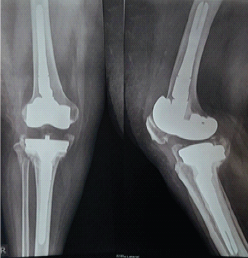

Flexor Carpi Radialis Tendon Stabilization for Chronic First Carpometacarpal Joint Instability: Clinical Outcomes from a Case Report

Akshay Punekar , Santosh D Ghoti , Mohammed Amjad Sohiel , Niranjan Sunil Ghag , Alok Yadav , Aditya A Agarwal